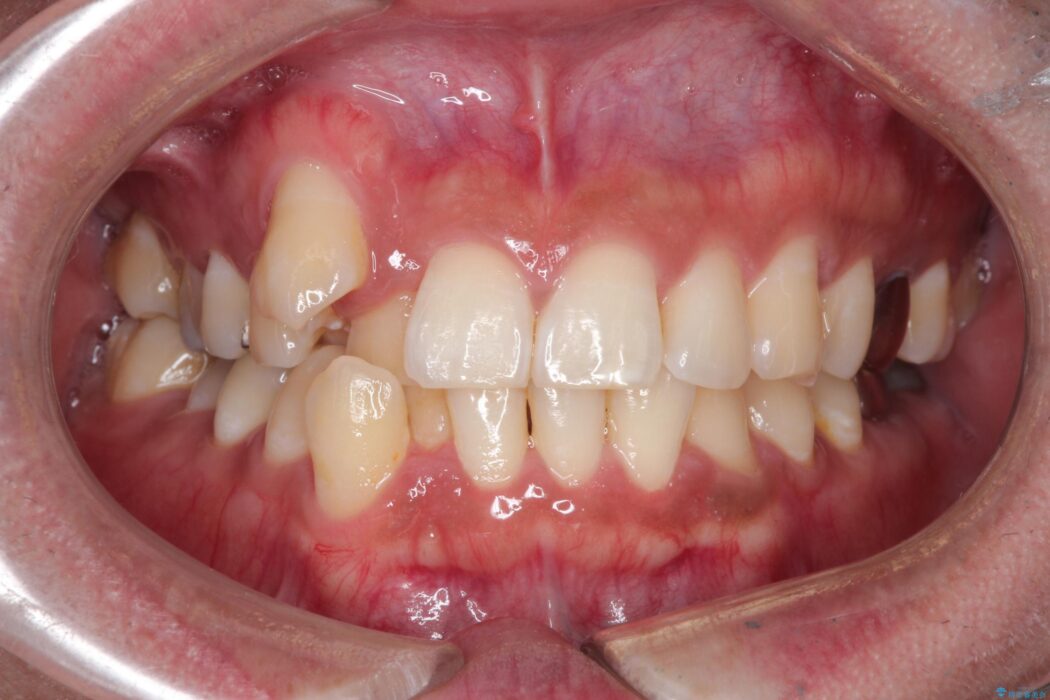

噛み合わせのズレが右側で大きかった(2級)ため、右側上下2本の歯を抜歯し、ワイヤー矯正で噛み合わせを左右対称の理想的な位置に改善しました。

気になっていた八重歯や凸凹が改善され、大変ご満足いただけました。